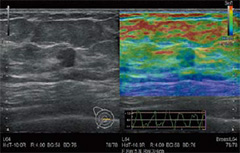

Elastography

・Real-time Tissue Elastography(RTE)

組織のひずみをリアルタイムに算出することで,硬さの違いを色付け表示します。乳腺領域をはじめ,甲状腺,泌尿器など,幅広い臨床分野での応用が可能です。

さらに,コンベックスプローブを用いてC型肝炎における肝炎Stagingの推定値(LF INDEX)を算出することも可能です。